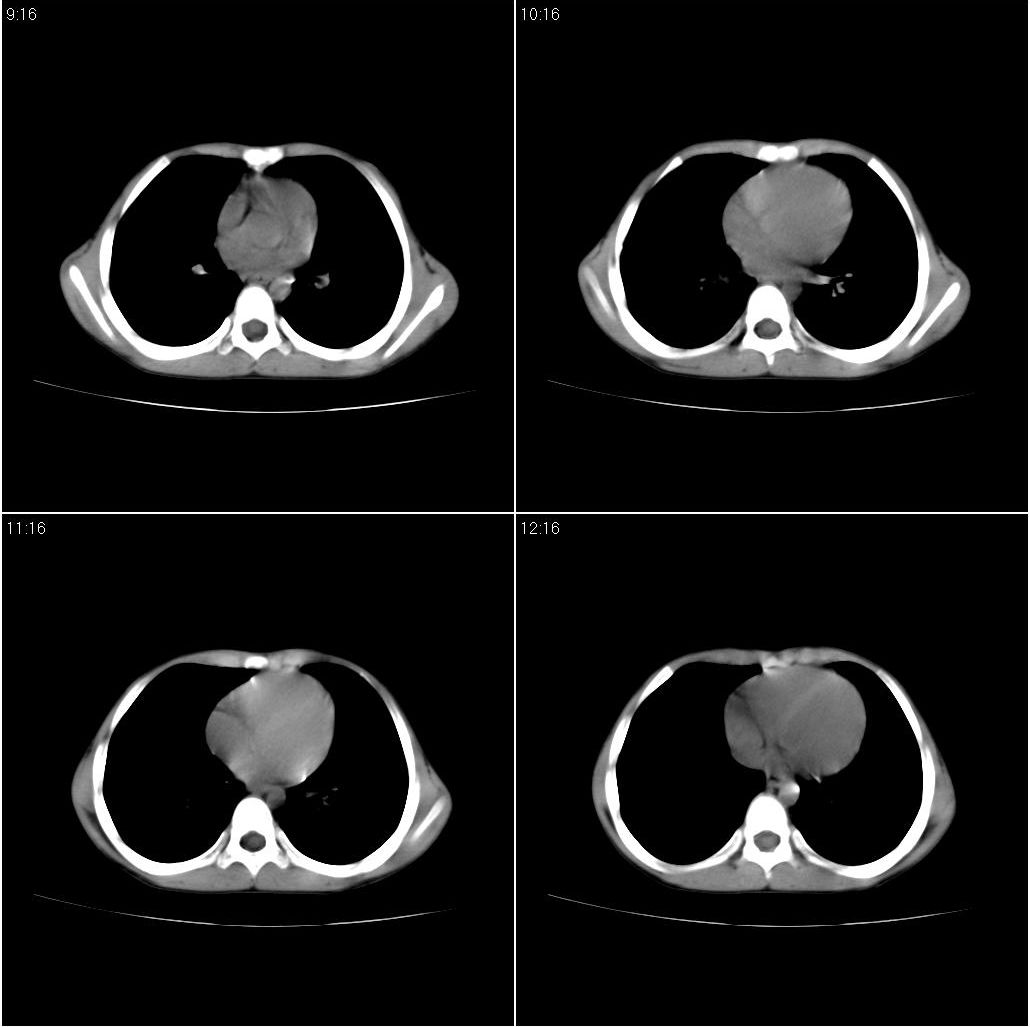

9月20号ct检查情况:

右上肺有班片状条索状高密度影。右肺上叶支气管稍变窄。右前上纵隔有结节状软组织密度影。上腔静脉旁淋巴结肿大。病灶抗炎后扩大。考虑结核可能性大。

右上肺不均匀密度增高,体积变小,水平裂弧状上移,纵隔内有肿大的淋巴结。考虑:

1、右上肺炎(吸收期),纵隔淋巴结肿大压迫右上叶肺膨张不全

2、纵隔淋巴结结核不能排除